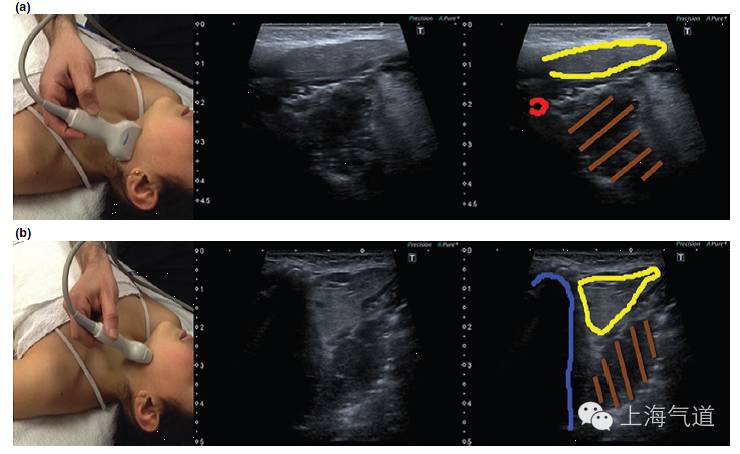

图3 a. 探头置于下颌骨水平取纵断面,黄色为颌下腺,红色为颈外动脉,棕色为扁桃体。b. 将探头旋转90度所得此区域的影像